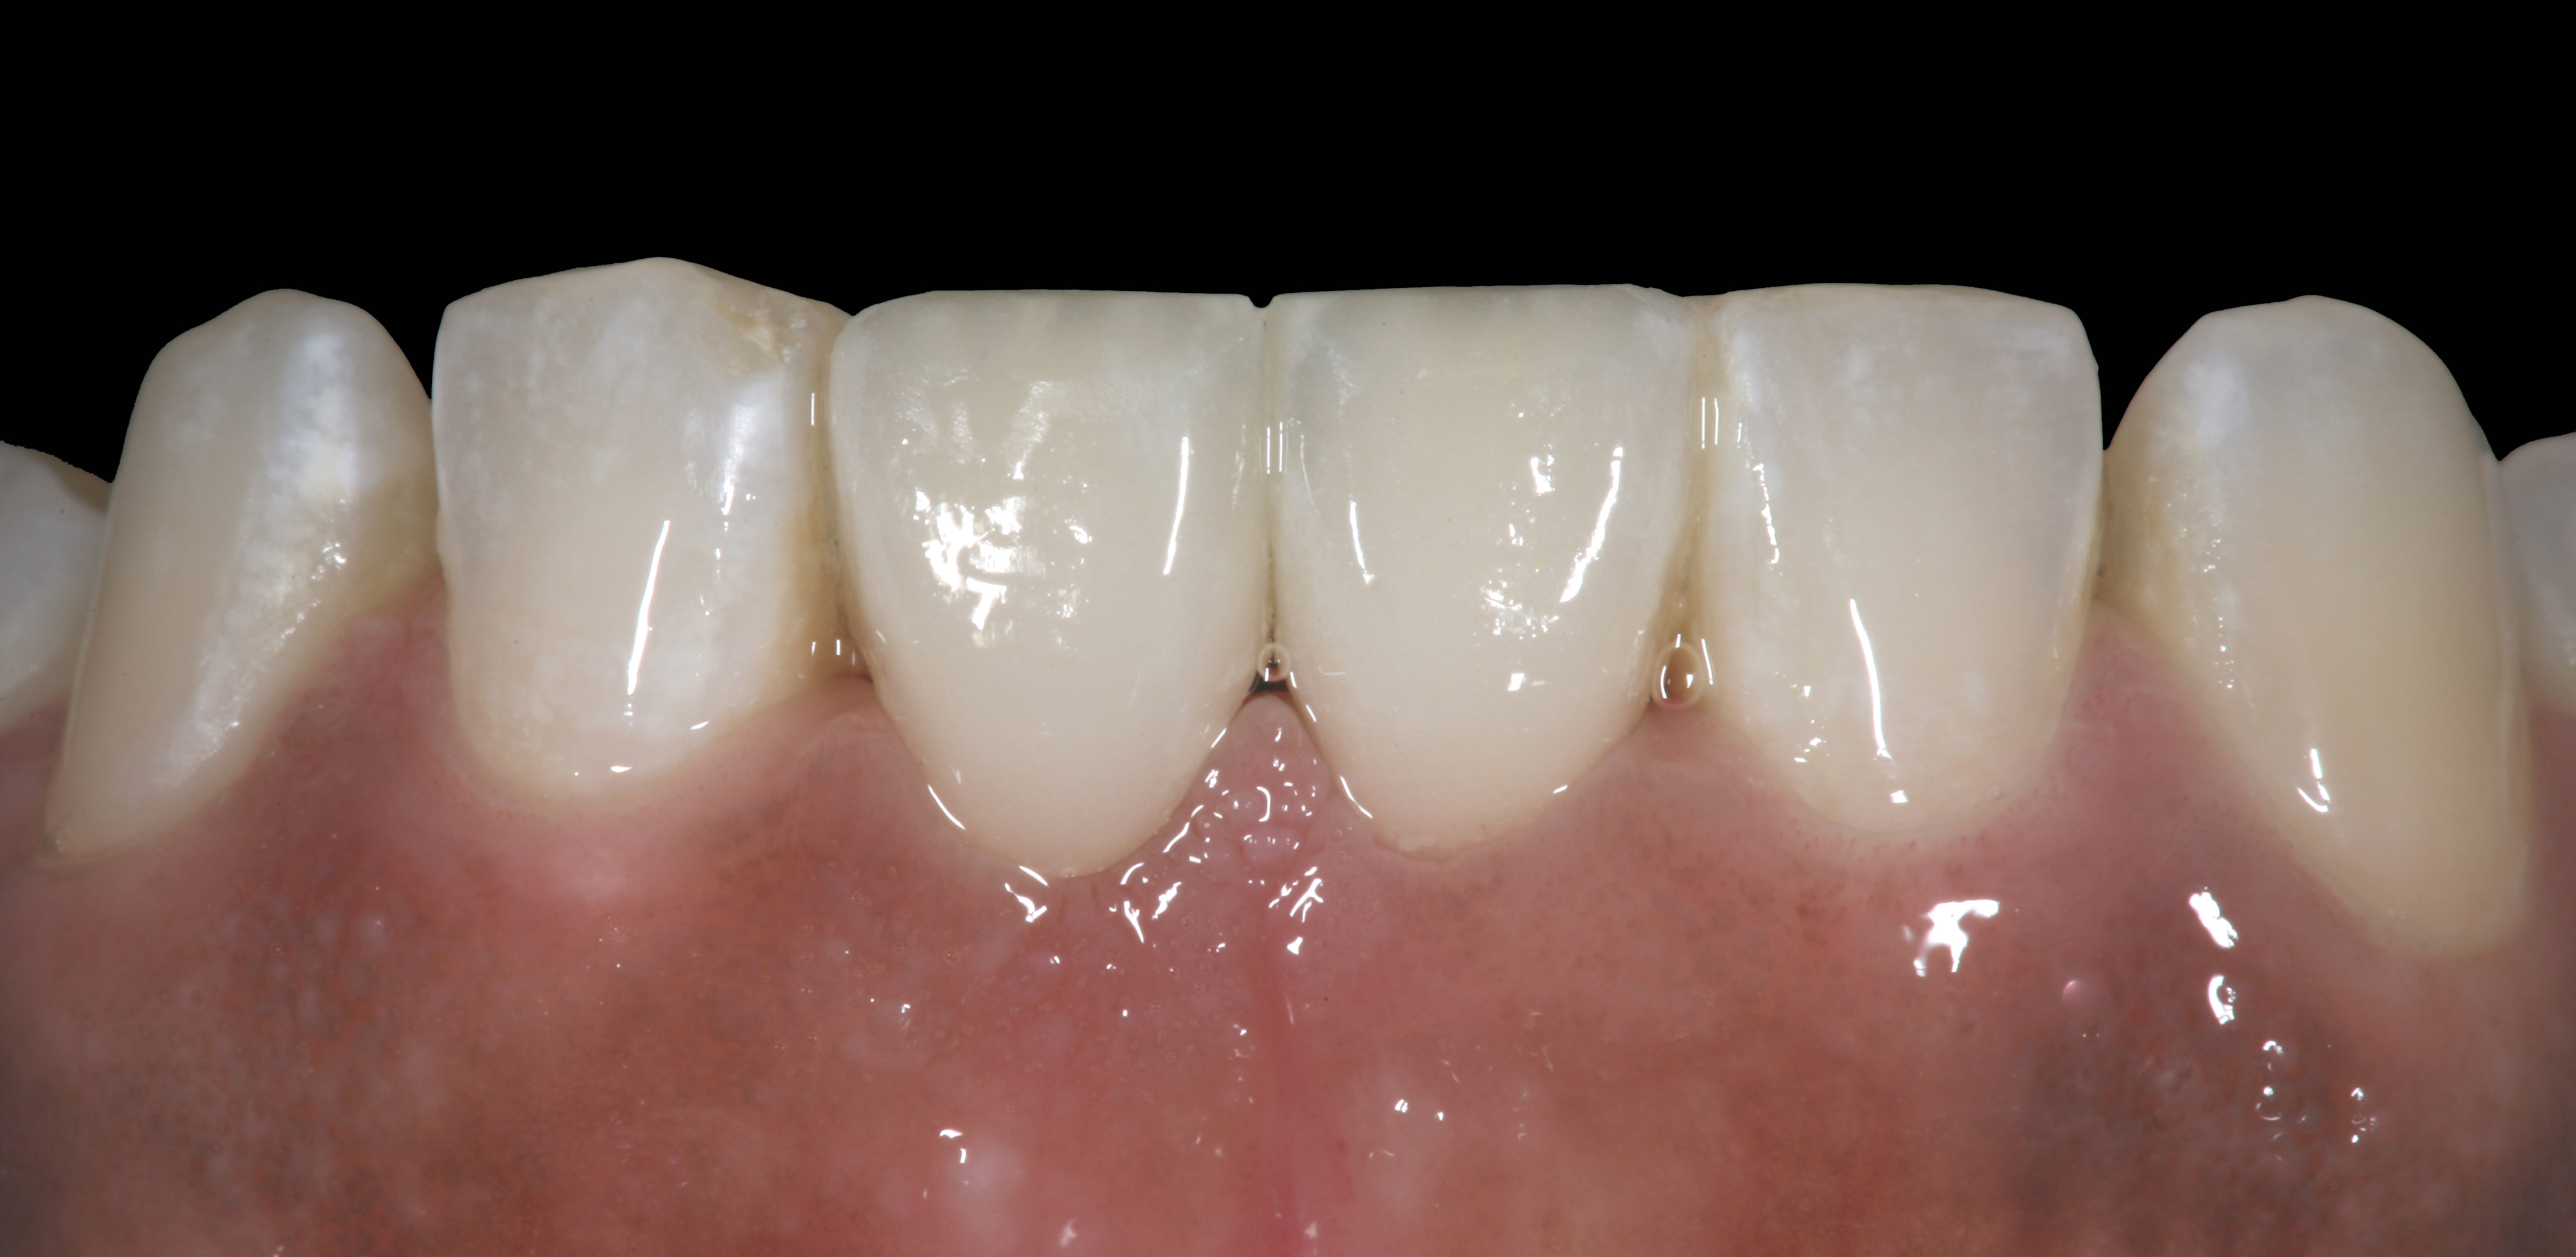

High-strength ceramic materials can be used in select cases to fabricate resin-bonded bridges to replace missing teeth as an alternative to removable prostheses or more invasive procedures such as conventional bridges or dental implants. The two missing lower central incisors (Figure 6) were replaced with two zirconia-based resin-bonded bridges (Figure 7). The single-retainer wing design has shown more than 94% clinical success after 10 years, which is significantly higher than the conventional two-retainer design (67.3% success).6 Proper bonding, however, is key for success and employs an air-particle abrasion step (Figure 8) followed by the application of a special ceramic primer (Figure 9). Figure 10 through Figure 12 demonstrate the clinical outcome.

The final restorative situation. (Restorative therapy by Dr. B. Wilk, Chalfont, PA.)

Figure 16